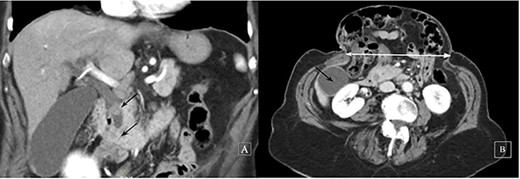

Abdominal U/S revealed the dilatation of the intrahepatic and extrahepatic bile ducts (common bile duct [CBD] diameter: 13 mm) and gallbladder (GB) sludge and the presence of a gallstone in the Hartmann’s pouch. Contrast-enhanced abdominal CT confirmed two iso-attenuating filling defects in the distal bile duct causing obstruction (Fig. 1). The CT also helped delineate the hernia as: contents, size and distance between rectus sheaths. ERCP with sphincterotomy and balloon dilatation was eventfully performed. The patient’s clinical course was uneventful and an elective LC was planned. Out of fear for complications the patient refused elective hernia repair.

Contrast-enhanced computed tomography: a coronal image revealing two iso-attenuating filling defects in the distal bile duct causing obstruction (black arrows) (A) and a subcostal axial slice of a giant incisional hernia (horizontal distance 14 cm, white line, GB, black arrow) (B)